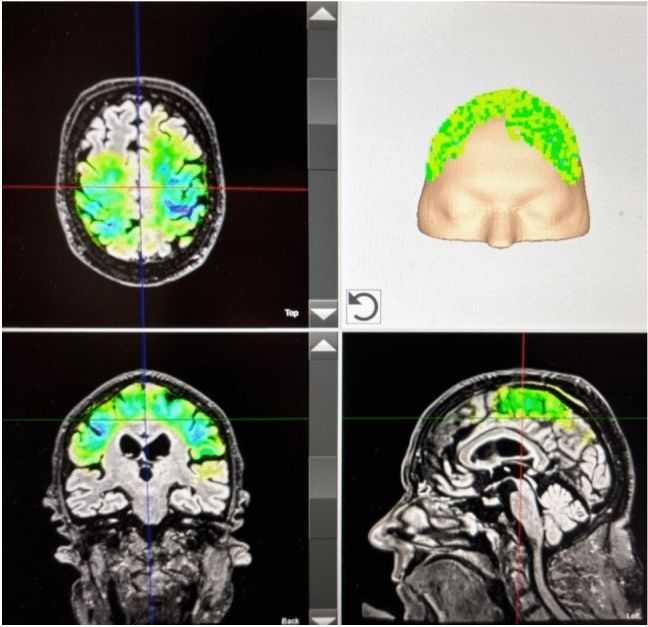

Transcranial Pulse Stimulation

Shock waves are acoustic pulses that have been successfully used since the end of the 1980s to treat various clinical symptoms, such as extracorporeal treatment of kidney stones, diseases of the locomotor system, as well as pseudo-joints, to stimulate angiogenesis, in the case of abnormal wound healing and the treatment of angina. In the mid-1990s, the effectiveness of shock waves in neurological disorders such as post-traumatic contractions and spastic paralysis was recognized. In 2015, the first treatments were performed on patients with Alzheimer's disease at the University of Vienna. In 2018, transcranial impulse stimulation (TPS®) using the NEUROLITH® system received, as the only method of this kind, approval for the treatment of the central nervous system in patients with Alzheimer's disease. Other neurological conditions, such as Parkinson's disease, and psychiatric disorders, such as depression, are undergoing further clinical trials, research, and development.